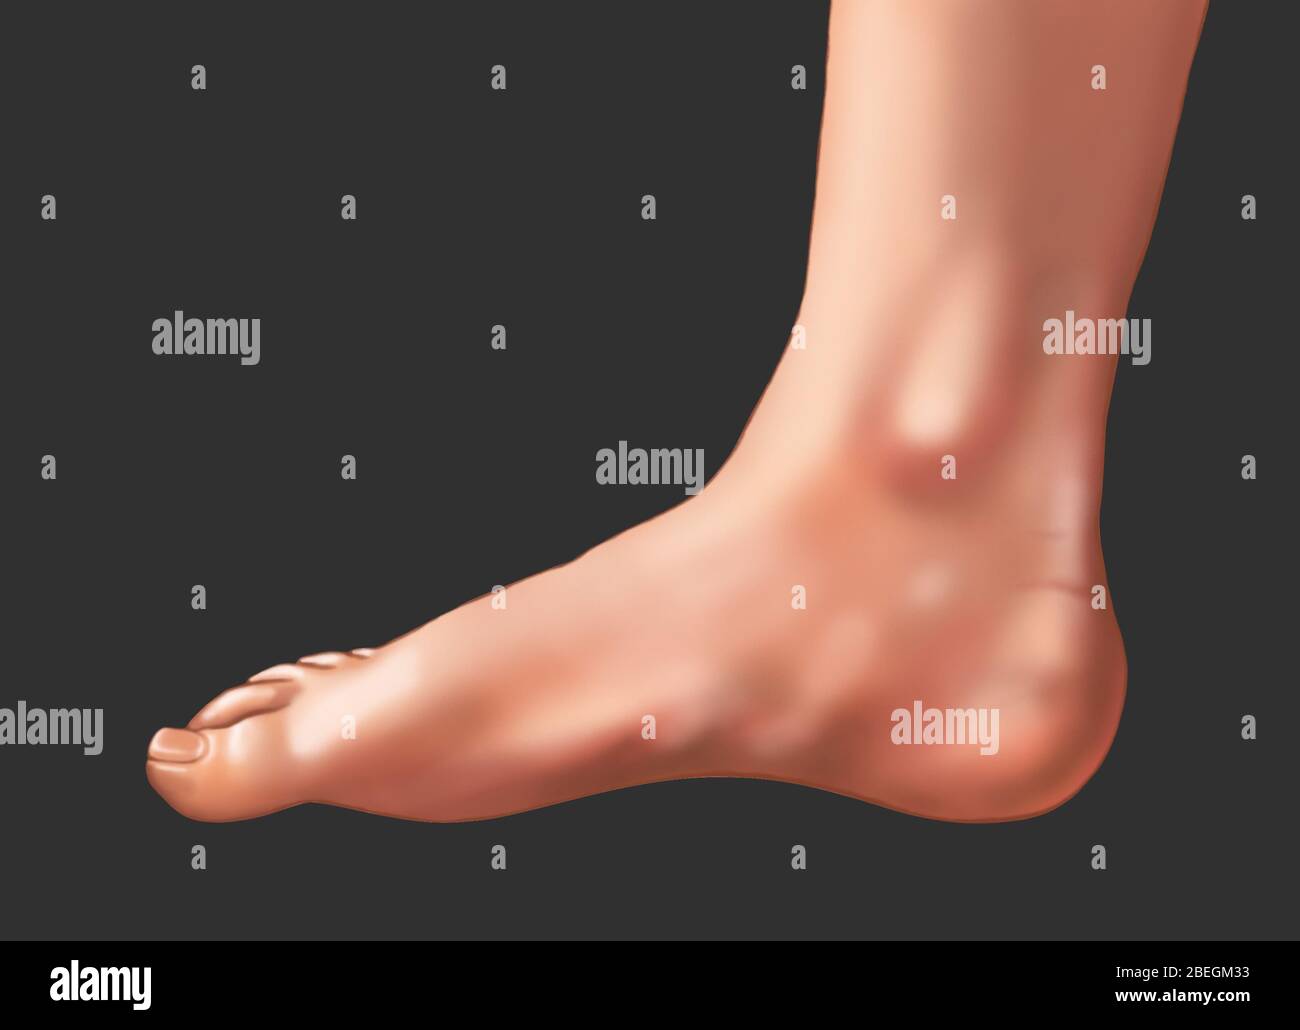

RF2FX3HF0–Fasciite plantaire. Illustration anatomie du pied humain expliquer sur le symptôme fasciite plantaire.